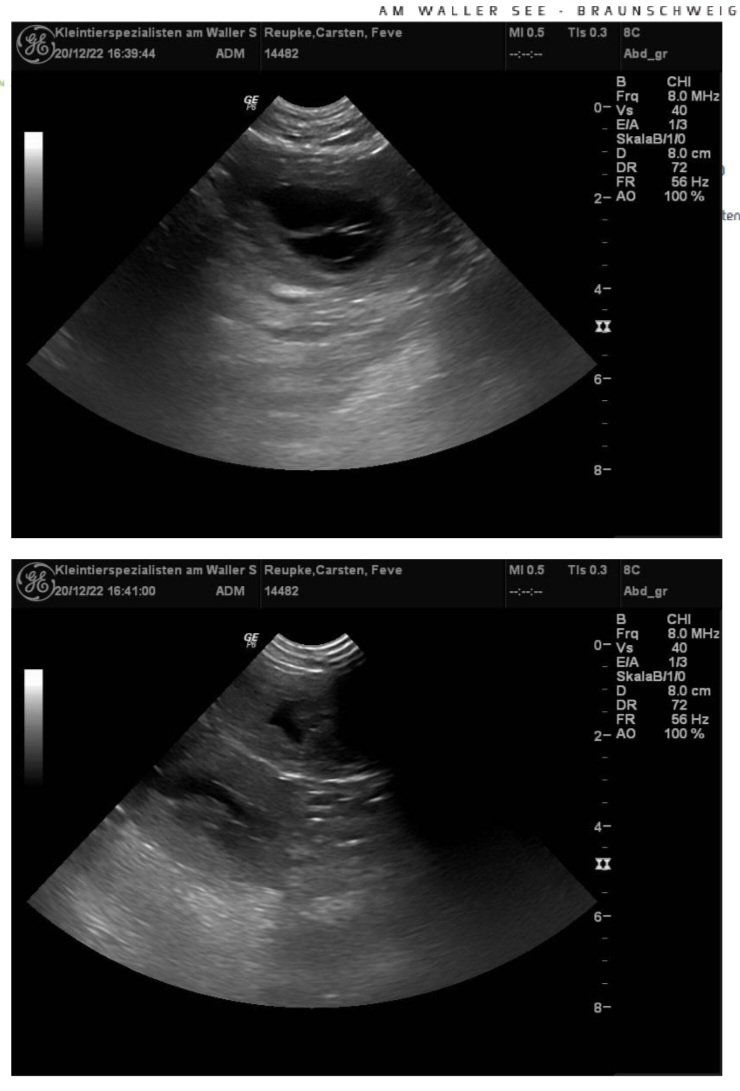

Seit dem 20.12.2022 haben wir nun Gewissheit.

Feve und Damon werden Eltern.

Ende Januar 2023 hoffen wir auf gesunde Welpen.

Am 20.12.22 wissen wir mehr.....